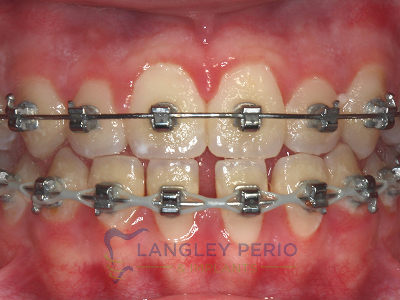

Case 2

Connective tissue grafting was done to cover exposed root surfaces to help to prevent root cavities from developing and reduce temperature sensitivity.